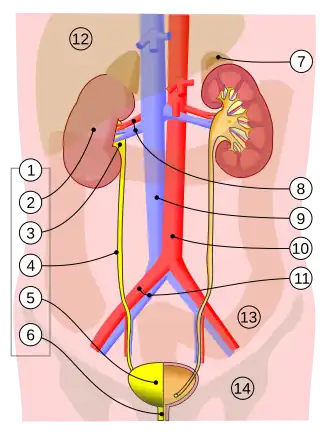

Vessels:

8. Renal artery and vein, 9. Inferior vena cava, 10. Abdominal aorta, 11. Common iliac artery and vein

With transparency:

12. Liver, 13. Large intestine, 14. Pelvis

The ureters are tubular structures, approximately 20–30 cm (8–12 in) in adults,[1] that pass from the pelvis of each kidney into the bladder. From the renal pelvis, they descend on top of the psoas major muscle to reach the brim of the pelvis. Here, they cross in front of the common iliac arteries. They then pass down along the sides of the pelvis and finally curve forward and enter the bladder from its left and right sides at the back of the bladder.[2] The ureters are 1.5–6 mm (0.06–0.24 in) in diameter[1] and surrounded by a layer of smooth muscle for 1–2 cm (0.4–0.8 in) near their ends just before they enter the bladder.[2]

A number of structures pass by, above, and around the ureters on their path down from the kidneys to the bladder.[2] In its upper part, the ureter travels on the psoas major muscle and sits just behind the peritoneum. As it passes down the muscle, it travels over the genitofemoral nerve. The inferior vena cava and the abdominal aorta sit to the midline of the right and left ureters, respectively.[2] In the lower part of the abdomen, the right ureter sits behind the lower mesentery and the terminal ileum, and the left ureter sits behind the jejunum and the sigmoid colon.[2] As the ureters enter the pelvis, they are surrounded by connective tissue, and travel backward and outward, passing in front of the internal iliac arteries and internal iliac veins. They then travel inward and forward, crossing the umbilical, inferior vesical, and middle rectal arteries.[2] From here, in males, they cross under the vas deferens and in front of the seminal vesicles to enter the bladder near the trigone.[2] In females, the ureters pass behind the ovaries and then travel in the lower midline section of the broad ligament of the uterus. For a short part, the uterine arteries travel on top for a short (2.5 cm (1 in)) period. They then pass by the cervix, traveling inward towards the bladder.[2]